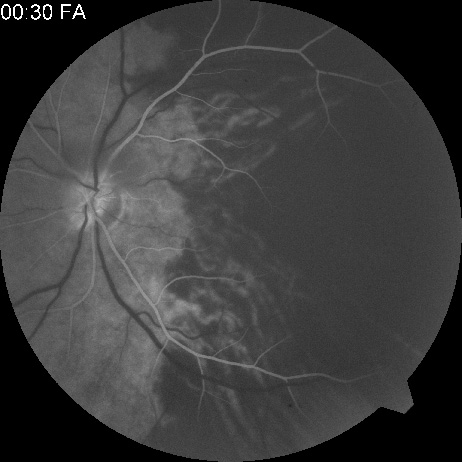

Another type of chronic ophthalmic artery obstruction produced by hypoperfusion caused by stenosis or occlusion of the ipsilateral extracranial carotid artery was first reported by Hedges170 and termed venous stasis retinopathy by Kearns and Hollenhorst.171 Venous stasis retinopathy is probably not a good term for this condition, however, because the basic mechanism involves reduction of the arterial inflow, not the venous outflow. Even more confusion has resulted from the use of the term to describe the features of the nonischemic form of central retinal vein obstruction.172 A better term is hypoperfusion or hypotensive retinopathy.172 Klijin and co-workers414 found this type of chronic ocular ischemia in approximately one-third of patients studied with symptomatic carotid artery occlusive disease.

Hypoperfusion retinopathy is characterized by dot and blot hemorrhages in the midperiphery of the fundus, by venous tortuosity and engorgement, by microaneurysms, and by the occasional sludging of blood within the veins. Fluorescein angiography may show areas of capillary nonperfusion; it may also show microaneurysms in the midperiphery and slow arm to retina or arteriovenous transit time (Fig. 9A and 9B).174 The condition does not usually affect the posterior pole, and patients typically have normal visual acuity, although an occasional patient may have macular edema.174 The entire periphery of the eye is usually affected, although there may be more hemorrhages in one quadrant than another. Patients occasionally experience ocular discomfort or eye pain despite normal intraocular pressure. Reduction of the ophthalmic arterial pressure is a pathognomonic feature. Disc edema and disc collaterals are generally not present. The electroretinogram shows abnormalities in both the a- and b-waves (see Fig. 9C).

Fig. 9. Intravenous fluorescein angiogram of a patient with hypotensive or hypoperfusion retinopathy. A: There is a marked delay in the choroidal and retinal filling. B: In the recirculation of the angiogram, there is a characteristic staining of both arteries and veins. C: Electroretinogram shows normal a- and b-waves in the normal right eye (upper tracing) and marked redirection of the a- and b-waves in the affected left eye (lower tracing).